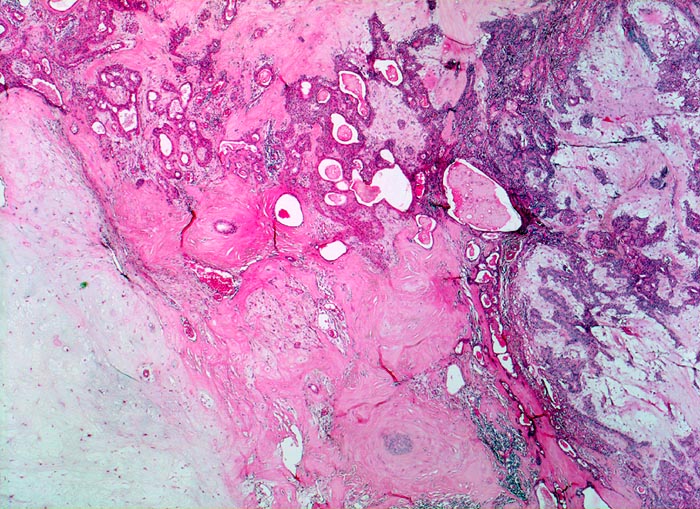

Mikroskopie und Histogenese:

Die architektonischen und zytologischen Befunde sind äusserst variabel. Pleomorphe Adenome bestehen aus einer duktalen epithelialen, einer myoepithelialen und einer mesenchymalen Komponente mit myxoider, hyaliner, chondroider oder ossärer Differenzierung. Der Prozentuale Anteil der verschiedenen Komponenten ist von Tumor zu Tumor sehr unterschiedlich. Gangstrukturen werden von einem einreihigen duktalen Epithel ausgekleidet. Das Gangepithel kann eine Plattenepithelmetaplasie mit Verhornung zeigen. Die Myoepithelzellen umgeben die epithelial ausgekleideten Gangstrukturen, bilden Nester, solide Zellplatten, Trabekel oder liegen einzeln im mesenchymalen Stroma. Die Morphologie der Myoepithelien ist sehr variabel (spindelig, plasmazytoid, epitheloid, sternförmig oder basaloid).

Histogenetisch handelt es sich wahrscheinlich um einen rein epithelialen Tumor, dessen mesenchymale Komponente von den neoplastischen Myoepithelzellen gebildet wird.

• Scharf begrenzter bekapselter Tumor bestehend aus epithelialen, myoepithelialen und mesenchymalen Anteilen.

• Das Epithel bildet duktale Strukturen, welche von reichlich Myoepithelien umgeben werden.

• Epitheiale Gänge werden ausgekleidet von kubischen luminalen Zellen und einer oder mehreren äusseren Schichten myoepithelialer Zellen.

• In den stromareichen Arealen rechts finden sich plasmazytoide Myoepithelzellen mit reichlich eosinophilem Zytoplasma und einem exzentrisch gelegenen runden Kern.

• Die stromale Komponente ist teils mukoid, teils hyalinknorplig, teils hyalinisiert bindegewebig.

• Oben im Präparat dem Tumor kappenförmig aufsitzende seromuköse Speicheldrüse (Glandula submandibularis). Das sollte der Kliniker dem Pathologen mitteilen: